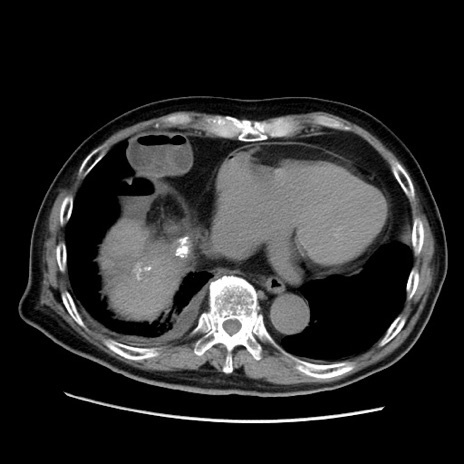

症例21(横断像)

【症例】70歳代男性

【主訴】腹痛

【現病歴】肝硬変・肝細胞癌にてかかりつけの方。約9時間前に食後より腹痛出現。症状が徐々に増悪し、嘔吐出現したため来院。

【既往歴】肝硬変、肝細胞癌(RFA、TACE後)

【身体所見】意識清明、表情苦悶様、BT 36℃、BP 129/78mmHg、P 88bpm、SpO2 97%(RA)、右上腹部から心窩部にかけて圧痛あり、反跳痛なし、筋性防御あり。

【データ】WBC 5800、CRP 0.16